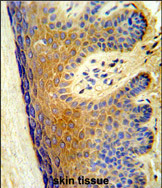

Supportive validation

- Submitted by

- GeneTex (provider)

- Main image

- Experimental details

- Formalin-fixed and paraffin-embedded human skin tissue reacted with PSMD13 Antibody (C-term) (GTX80499), which was peroxidase-conjμgated to the secondary antibody, followed by DAB staining. This data demonstrates the use of this antibody for immunohistochemistry.